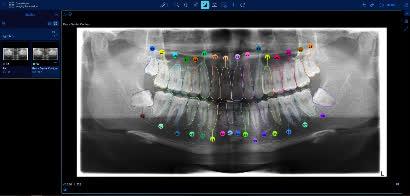

“AI+医疗创新”展区展示卫生署概念验证项目“从人工智能诊断到自动化牙科图表”,利用先进的半监督对比学习方法,以AI解读牙科X光影像,验证了将影像分析转化为结构化资料,自动生成牙科图表,并与临床管理系统整合的潜力。展望最终成果可减少人手资料输入、降低错误率,节省宝贵临床时间,迈向智慧化、一体化牙科护理。